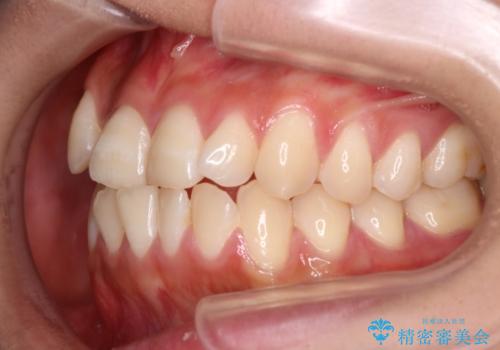

- 前歯のガタガタを主訴に来院されました。

インビザラインも提案しましたが、装着時間を確実に確保できるか不安ということもありワイヤー矯正を希望されました。